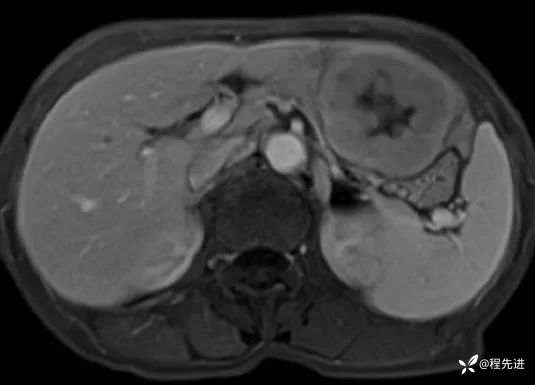

T1及T1增强4期: